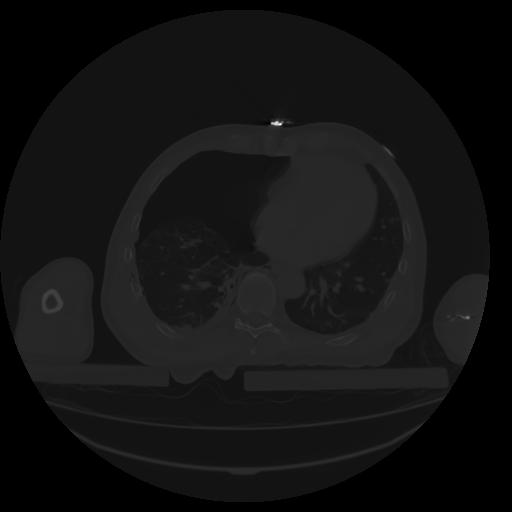

27 CUERPO,CE,Axial,3.0,CUERPO,,